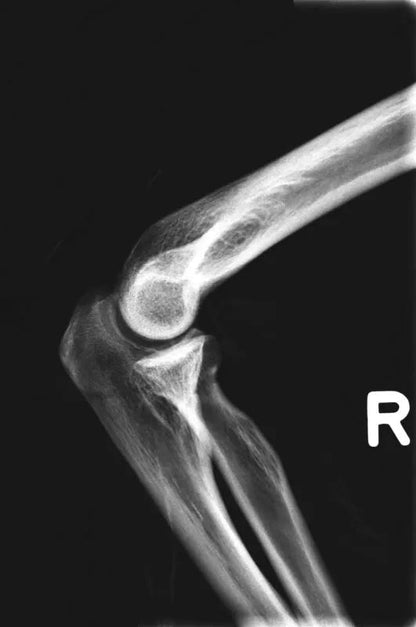

The whole-body X-ray phantom serves for practical training in projection radiography as well as in positioning and positioning techniques. It enables the production of realistic X-ray images under training conditions and depicts anatomical structures in their natural size.

The phantom contains a natural human skeleton. Additionally, the outlines of the larynx, lungs, heart, and kidneys are integrated, appearing as shadows on the X-ray images. This allows for the creation of images that accurately reflect the conditions found in patients. The use of a real skeleton enables the identification of bony landmarks that are not visible in plastic models.

The joints are mounted with full mobility, allowing positioning in common radiological standard positions, including special positions such as the frog position and pronation and supination of the forearm. The arms can be raised, so the phantom can also be used for bone examinations in CT scans. Particular attention was paid during assembly to the realistic representation of the joint spaces.

Each phantom is a handcrafted, unique piece. Variations in size, design, and appearance are possible. Depending on the model, pathological findings may be present. The revised design was developed in collaboration with a German training institution for medical-technical radiology assistants and meets the requirements of modern training concepts.